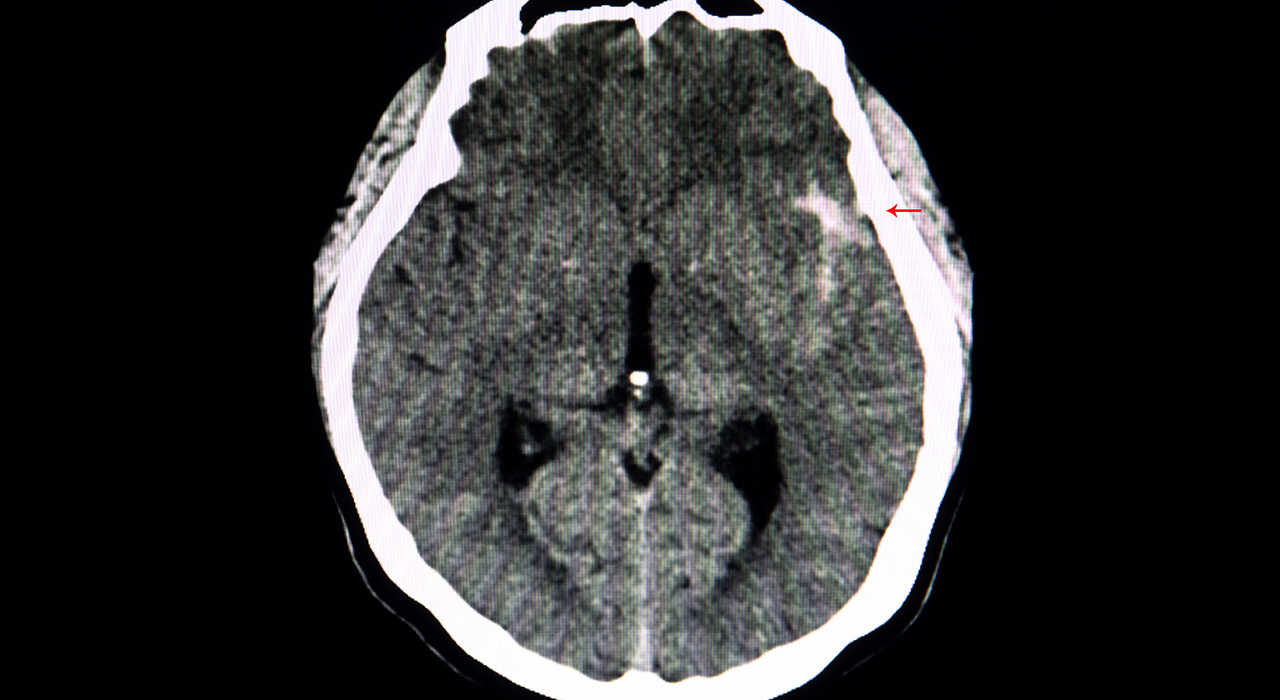

Como fue expuesto con anterioridad, debe suponerse que toda cefalea de comienzo brusco e inusual es una hemorragia subaracnoidea hasta que se demuestre lo contrario. El estudio de elección es la TC de cerebro, con una sensibilidad del 95 % en las primeras 24 horas, disminuyendo paulatinamente en los días subsiguientes a medida que la sangre se torna isodensa con el parénquima cerebral. Así a los tres días es del 80 %, a los cinco días 70 %, a la semana 50 % y a las dos semanas del 30 %. Es válido tener en cuenta que la hiperdensidad espontánea de la sangre en la TC depende de la concentración de hemoglobina por lo que en caso de existir anemia con una concentración de hemoglobina por debajo de 10 g/dl la misma será isodensa con el parénquima cerebral.

Cabe destacar la importancia de la técnica en la realización de la TC, recomendándose cortes finos (3 mm entre cortes) a nivel de la base del cráneo, ya que cortes más gruesos (10 mm) ocultan pequeñas colecciones. Por otro lado la habilidad en la correcta identificación de hemorragia en la TC varía ampliamente entre médicos emergentólogos, neurólogos y radiólogos generales. Los médicos menos experimentados, indudablemente, pueden pasar por alto anormalidades sutiles. Teniendo en cuenta la distribución y la cantidad de sangre evidenciable en la TC de cerebro se puede clasificar a la hemorragia subaracnoidea según la escala de Fisher (Tabla 4).